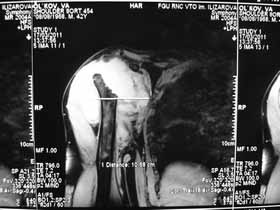

Не усмотрел в анамнезе "ноябре 2009 - травма с потерей сознания. В феврале 2010 г - первый рентген правого плечевого сутава - перелом анатомитеской шейки".

Поэтому желательно выставить все рентгенологические и данные МРТ для сравнения со снимками из статьи.

Думаю, коллеги будут не против увидеть рентген.

Извиняюсь, что-то фотографии сразу не прошли. сейчас исправимся.